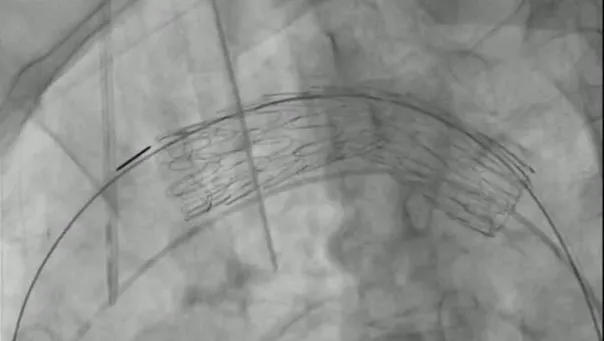

手技

右総大腿動脈に6 Frシースを留置し、アクセスとした 。ラジフォーカスTMガイドワイヤーM**および 5 Frピッグテールカテーテルを上行大動脈まで進行させ、manipulateしたEgoist® EGU35-AC300Q (Arch Curve)ガイドワイヤーを大動脈基部まで到達させた。この時点で透視下にガイドワイヤー押し付けを行い、安定した状態で大弯側に押し付け可能なこと、左室内へ迷入しないことを確認した。22 Frゴア®ドライシール フレックス イントロデューサシースを進行させ、引き続きTAG® コンフォーマブル ステントグラフトTGMR373710Jを適正位置まで進行させた。DSAを施行し、左総頚動脈(LCCA)および左鎖骨下動脈(LSCA)の位置を確認した。ここからは、術者(ドライシールシース固定およびデリバリーカテーテルの操作)・助手(デリバリーカテーテルの固定、ガイドワイヤーの押し付け)の共同操作にて一次・完全展開を行った。ガイドワイヤーを軽く押し付けた状態で、パーシャルアンカバーステントがLCCAに若干かかる位置で一次展開を施行した。ガイドワイヤーの押し付けを加えて、LCCA直下にパーシャルアンカバーステントが位置するように微調整を行った。DSA上のZone 2レベルの小弯側に合わせて、アンギュレーションコントロールダイヤルを回転させて至適な角度に調整した。ガイドワイヤーを押し付けた状態で完全展開を施行した。DSAを施行し、コアキシャルに留置されていること、特に小弯側が至適角度で留置されていることを確認し、この時点でのアンギュレーションコントロールは必要ないと判断した。ガイドワイヤーを用いて、慎重にピッグテールカテーテルを抜去し、引き続き完全展開を施行した。DSAを施行し、エンドリークが無いことを確認した。左上腕動脈よりアクセスし、LSCA根部で造影した。DSA上、明らかなType ll エンドリークを認めず、deployment sleeve部分を含むステントグラフトにてLSCA根部が完全に被覆・閉鎖されていることが確認できた。